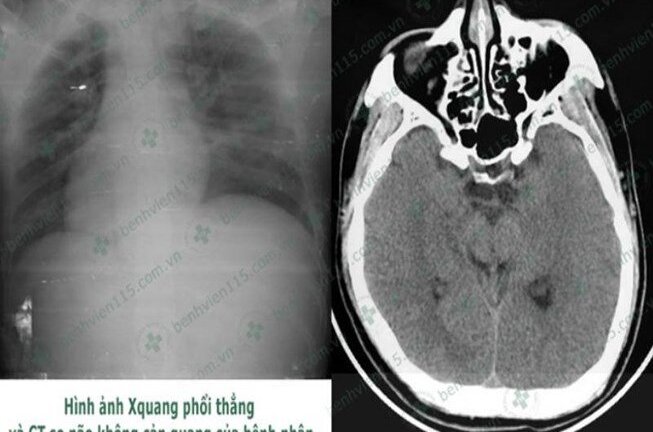

Sáng 17/12, Bệnh viện Nhân dân 115 TP.HCM vừa cấp cứu tài xế bị bệnh tiểu đường, hạ đường huyết nghiêm trọng dẫn đến hôn mê sâu do quên ăn sáng.